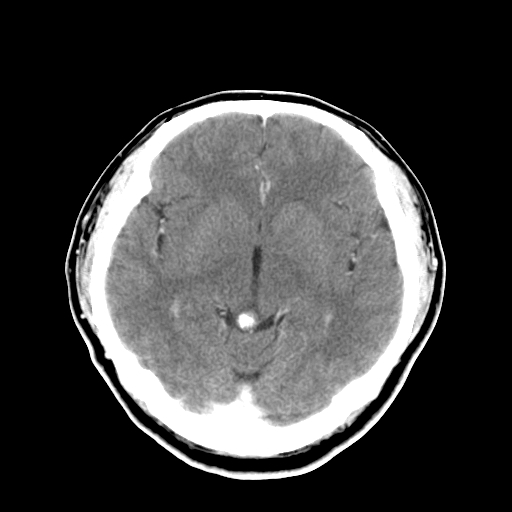

标题: CT16447B:(续)增强扫描图像。 [打印本页]

标题: CT16447B:(续)增强扫描图像。

患者今日做ct增强检查,现补传增强扫描图像。

松果体钙癍增大,无其他改变,定不了性

未见明确异常。